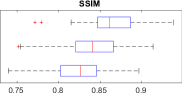

Image Quality Assessments: We compare HR ground-truth 3D volumes with upsampled LR raw data by measuring PSNR, SSIM and cross-correlation. We report SSIM, in particular, due to the well-understood metric properties that afford assessment of local structure correlation and reduced noise sensitivity. LR test imagery is upsampled in-plane () by factors of , to align with target ground-truth resolution. Quality metrics in Fig. 1 report improvements observed for an image upsampling factor of . This provides initial evidence in support of our hypothesis; learning problem and sensor specific deconvolutional filters to perform MRI stack upsampling is of benefit for subsequent resolution-sensitive tasks such as motion compensation and HR volume reconstruction.

By learning problem specific HR synthesis models, our 3D MRI CNN strategy outperforms the naïve baseline up-sampling, quantitatively improving the quality of the inferred HR imagery. Fig. 2 exhibits an example of qualitative improvement in orthogonal fetal MRI test-stack axes.